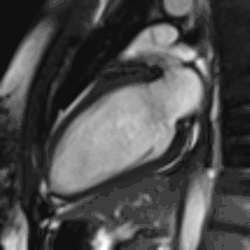

Late gadolinium enhancement

Gadolinium-based contrast agents are administered intravenously and delayed imaging is performed at least 10 minutes later to achieve optimum contrast between normal and infarcted myocardium. An inversion recovery (IR) sequence is used to null the signal from normal myocardium. Myocardial viability can be assessed by the degree of transmural enhancement. Cardiomyopathic, inflammatory and infiltrative diseases may also have distinctive patterns of non-ischemic LGE.[22][23]

Myocardial infarction. Imaging in the 4-chamber plane. Left: Inversion recovery LGE sequence. Right: Corresponding cine sequence. This shows a chronic infarction with akinetic apex and transmural scar. Mitral regurgitation is also present.